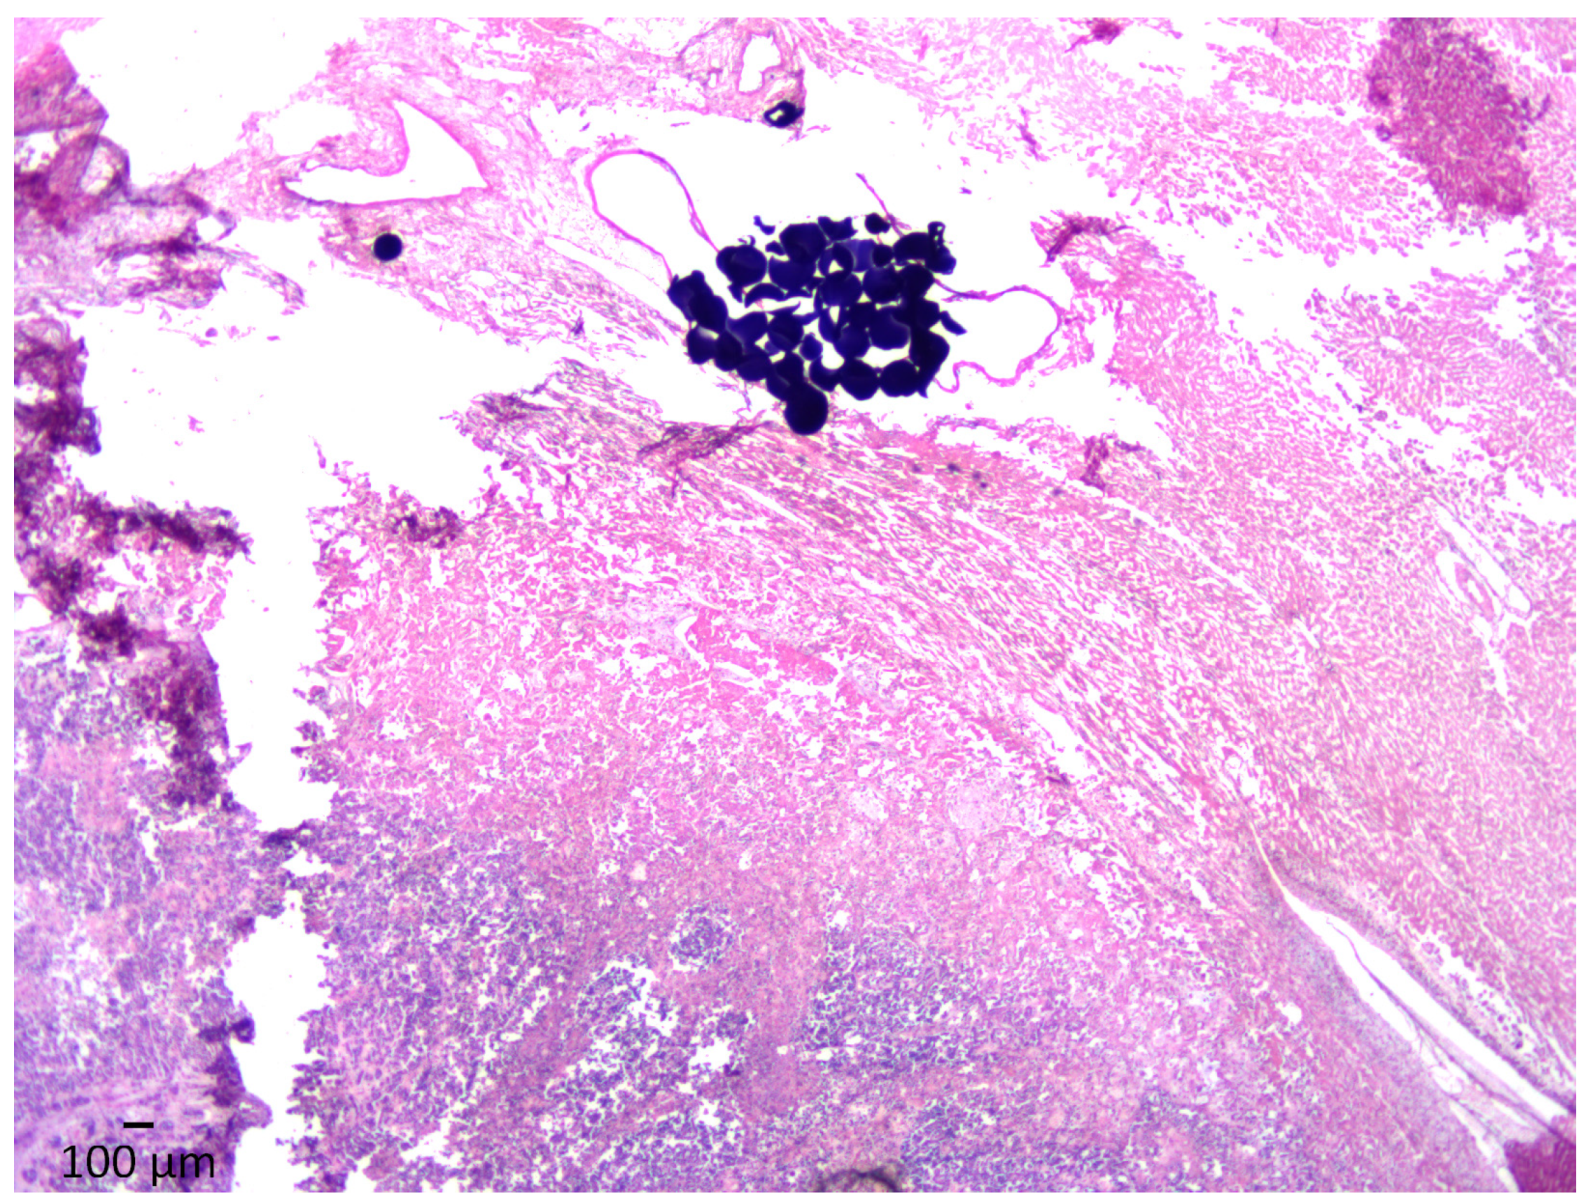

3.3. Histopathology